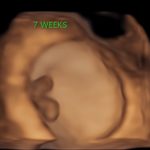

4D/5D/HD Ultrasound Gallery

Gallery